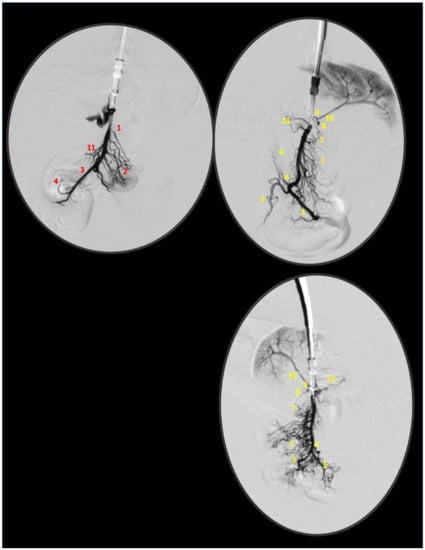

2.4. Venography

2.5. Superior Sagittal Sinus, Portal, Superior Mesenteric and Caval Vein and Abdominal Aorta Pressure Recording